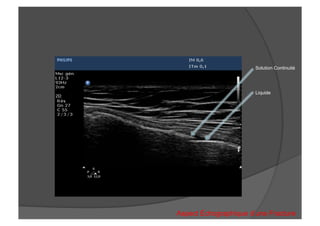

Solution Continuité

Liquide

Aspect Échographique d’une Fracture